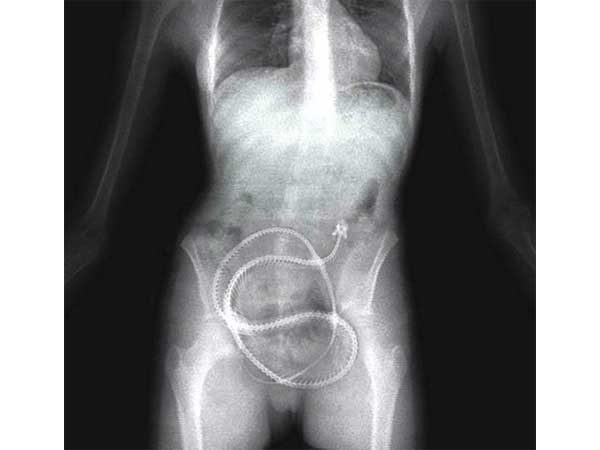

Live Eel

Lolz! This is the funniest of all. A man from China admitted himself to a hospital when he accidentally got a live eel stuck inside his anus. He said that he was inspired by the porno world so much that he wanted to try something unique. Doctors claim that the eel was alive when the man was being operated, but it died shortly after it was removed.